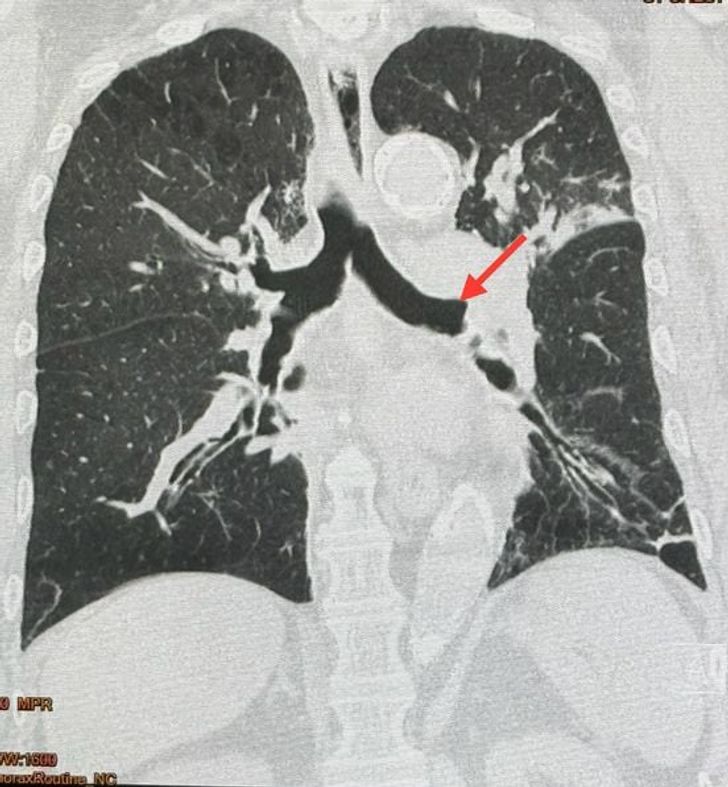

นพ.มนูญ ระบุว่า ผู้ป่วยชายอายุ 87 ปี เป็นโรคหัวใจ เบาหวาน ความดัน ไขมันในเลือดสูง โรคถุงลมโป่งพอง มีประวัติสำลักอาหารบ่อย ปลายเดือนมีนาคม 2567 เริ่มมีไข้ ไอ มีเสมหะ เอกซเรย์ปอดมีฝ้าขาวกลีบบนด้านซ้าย ให้ยาปฏิชีวนะรักษาปอดอักเสบติดเชื้อ ดีขึ้นชั่วคราว แล้วก็กลับมาเป็นซ้ำอีก จึงทำคอมพิวเตอร์ปอดวันที่ 25 เมษายน พบหลอดลมของปอดข้างซ้ายบนอุดตัน และปอดกลีบบนข้างซ้ายอักเสบและแฟบเล็กน้อย วันที่ 1 พฤษภาคม ได้ทำการส่องกล้องเข้าไปในหลอดลม เห็นสิ่งแปลกปลอมสีเหลืองผิวเรียบอุดปิดหลอดลมของปอดข้างซ้ายด้านบน ไม่สามารถคีบเอาสิ่งแปลกปลอมออกได้ ตัดชิ้นเนื้อก้อนนี้ส่งตรวจทางพยาธิวิทยา อ่านว่าเป็น “พืช”